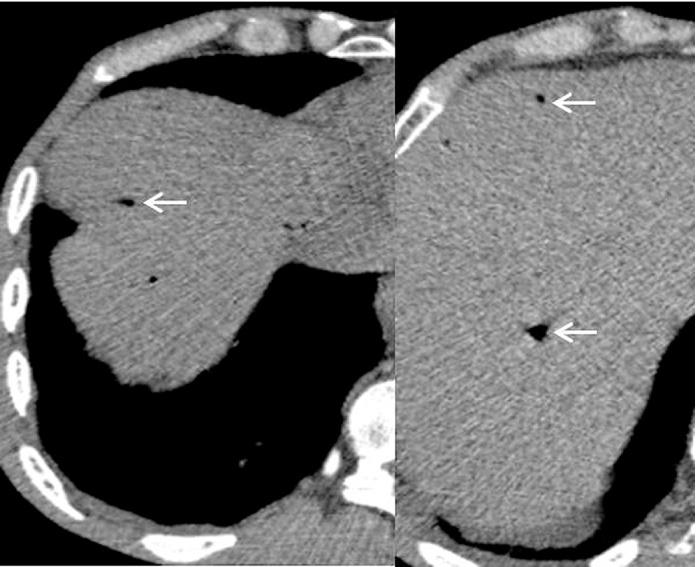

Etiologies were mesenteric infarction (n=5), sigmoid diverticulitis (n= 1), septic shock (n=1), postoperative peritonitis (n=1), acute pancreatitis (n=1), iatrogenic cause (n=3) and idiopathic after a laparotomy (n=1). The outcome was fatal in for 6 patients. Abundance of HPV was expressed in total number of hepatic segments involved. The involvement of 3 or more segments was a sensitive sign for lethal outcome with high sensitivity (100%) but it was not specific (50%). Negative predictive value of this sign was 100% (p≤0.005). Positive predictive value of PI for death was 100% (p≤0.001).

The first etiology radiologists should look for in front of HPVG involving more than 3 hepatic segments and associated with PI is intestinal necrosis which announces a poor prognosis. This study shows that outside of shock situations, HPVG involving 2 or less hepatic segments without PI predicts a good outcome.

病因包括肠系膜梗死(n = 5)、乙状结肠憩室炎(n = 1)、感染性休克(n = 1)、术后腹膜炎(n = 1)、急性胰腺炎(n = 1)、医源性原因(n = 3)和剖腹术后特发性(n = 1)。6例患者预后为致命。HPV的丰度以受累肝段总数表示。3个或更多肝段受累是致命结局的敏感征象,敏感性高(100%)但不具有特异性(50%)。该征象的阴性预测值为100%(p≤0.005)。PI对死亡的阳性预测值为100%(p≤0.001)。

对于累及3个以上肝段且伴有PI的HPVG,放射科医生首先应寻找的病因是肠坏死,这预示着预后不良。本研究表明,在非休克情况下,累及2个或更少肝段且无PI的HPVG预示预后良好。